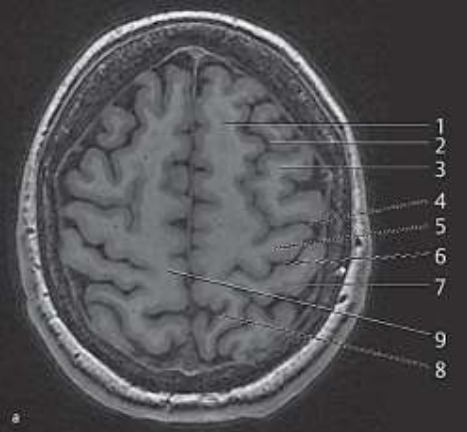

Com base na imagem de ressonância magnética a seguir e seus conhecimentos de neuroanatomia radiológica, assinale a alternativa que descreve corretamente o nome e a função da estrutura indicada pelo número 5

Enunciado 3027994-1